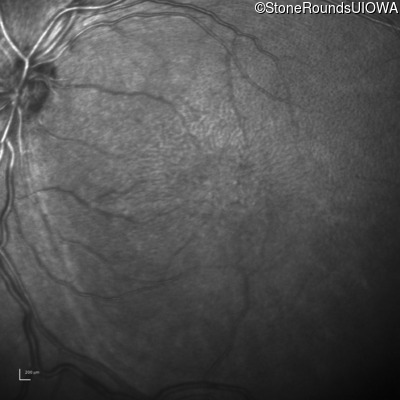

Infrared Fundus Photograph - Right - 10/40

Exemplar